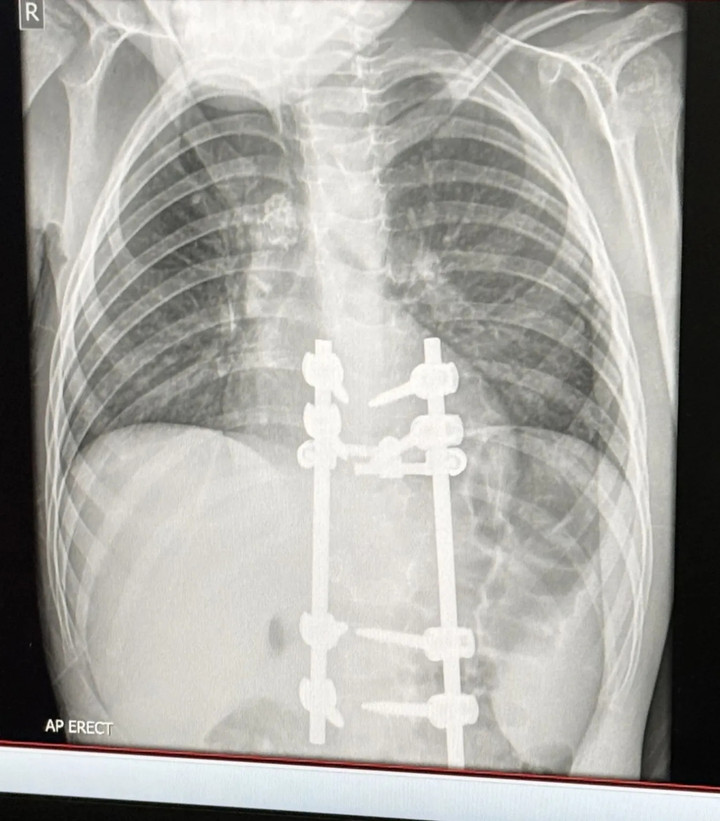

Mẹ phát hiện căn bệnh đáng sợ của con trai nhờ quan sát dáng đi bất thường- Ảnh 2.

Kết quả X-quang của Elliot sau phẫu thuật. (Ảnh: Kennedy News)

Sau khi đánh giá kỹ lưỡng, các bác sĩ chỉ định phẫu thuật đối với cậu bé Elliot, nhằm giải phóng chèn ép ống thần kinh và ổn định lại cấu trúc cột sống.

Ca phẫu thuật đầu tiên đã thành công, Elliot hiện có thể đi bộ, nhưng chưa được phép chạy nhảy. Cậu bé sẽ đối mặt với lần phẫu thuật thứ hai trong vòng sáu tháng tới, nếu dấu hiệu tổn thương lao trên cột sống không thu nhỏ. Theo chia sẻ từ người mẹ, dáng đi của Elliot đã trở lại bình thường, các cơn đau dữ dội ở vùng lưng cũng biến mất.